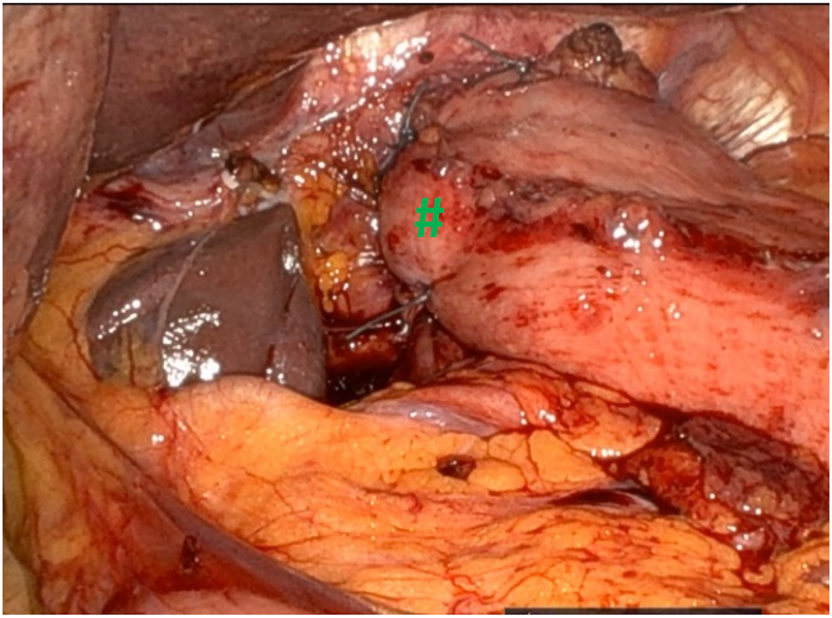

After dissection of the hernia sac and reduction of the hernia contents, the esophagus is mobilized in the posterior mediastinum in order to get a minimal intra-abdominal length of 3 cm (#). Next step of the procedure implies closing of the crural defect (*) using nonabsorbable interrupted sutures.